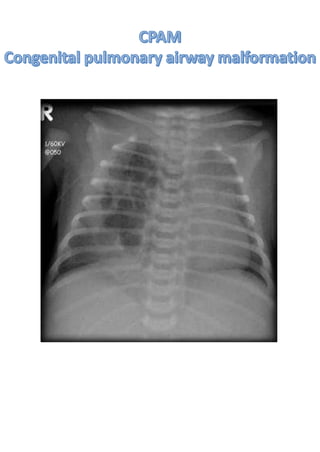

• 1.

X RAY BASICS Theinternational radiation symbol ‘’the trefoil’’ Discovery of X rays Father of radiology: Wilhelm roentgen 8th November 1895 © DR RALLAPALLI SPANDANA MD 10/10/2020